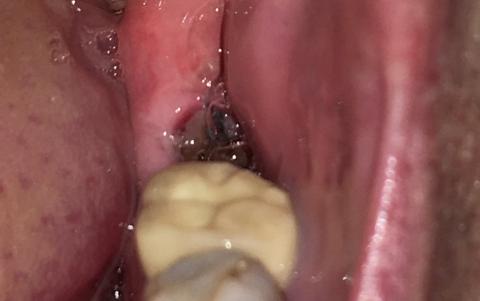

This analysis is based on the visual evidence in the image (which appears to show an exposed socket) and standard dental protocols for Alveolar Osteitis. Note: This is an analysis by an AI and is not a substitute for an in-person examination and diagnosis by a licensed dentist.

| Socket Appearance | The socket looks deep, and a dark, greyish/blackish material may be visible at the bottom . The area lacks the typical solid, dark red blood clot expected in a healing socket. | Loss of the blood clot exposes the underlying alveolar bone. This exposure causes severe pain because the bone and nerve endings are unprotected. |

| Surrounding Tissue | The gums (gingiva) appear red and possibly slightly inflamed around the extraction site. | Inflammation is common due to tissue irritation and exposure to oral bacteria, even if a true secondary infection has not fully set in. |